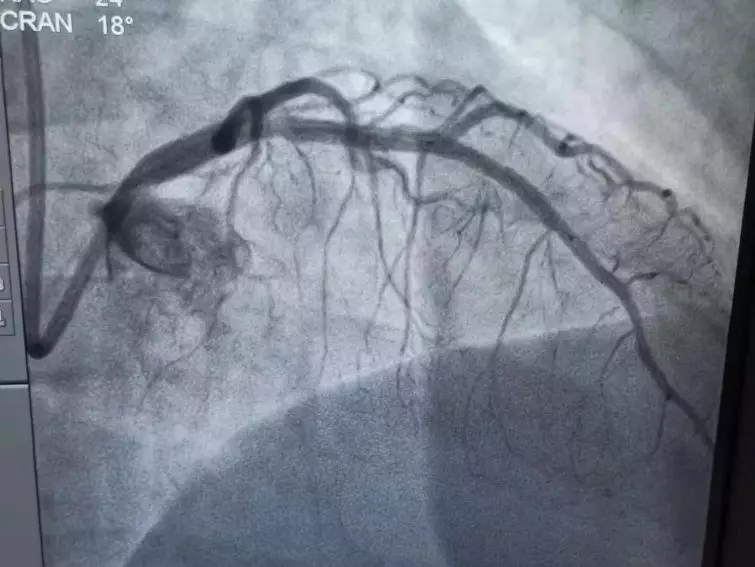

手术室内,李友文主任医师及其团队造影发现,左冠状动脉前降支,中远端100%堵塞,术中出现心肌顿抑,室颤给予电击复律恢复窦性心律,随后给予开通血管的介入治疗。